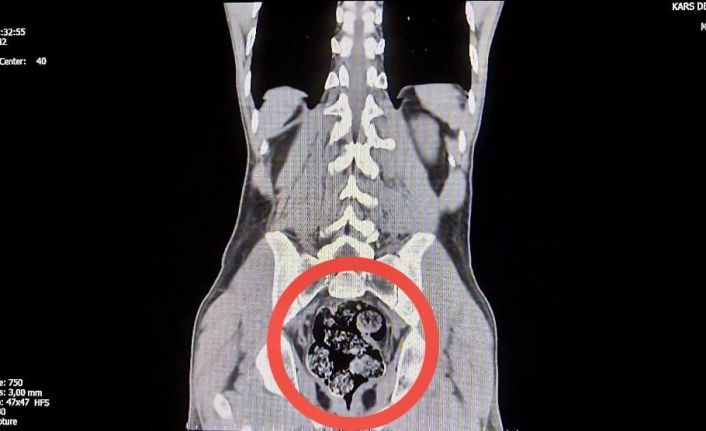

İl Emniyet Müdürlüğü’ne getirilen ve durumundan şüphelenilen kuryelerden Shekarbaghanı, detaylı arama için Kars Harakani Devlet Hastanesi’ne götürüldü. Hastanede yapılan emar ve röntgen kontrollerinde şüphelinin makatında cisim olduğu belirlendi. Yapılan cerrahi müdahalede, şüphelinin makatından 7 parça halinde 203,02 gram metamfetamin çıkarıldı.